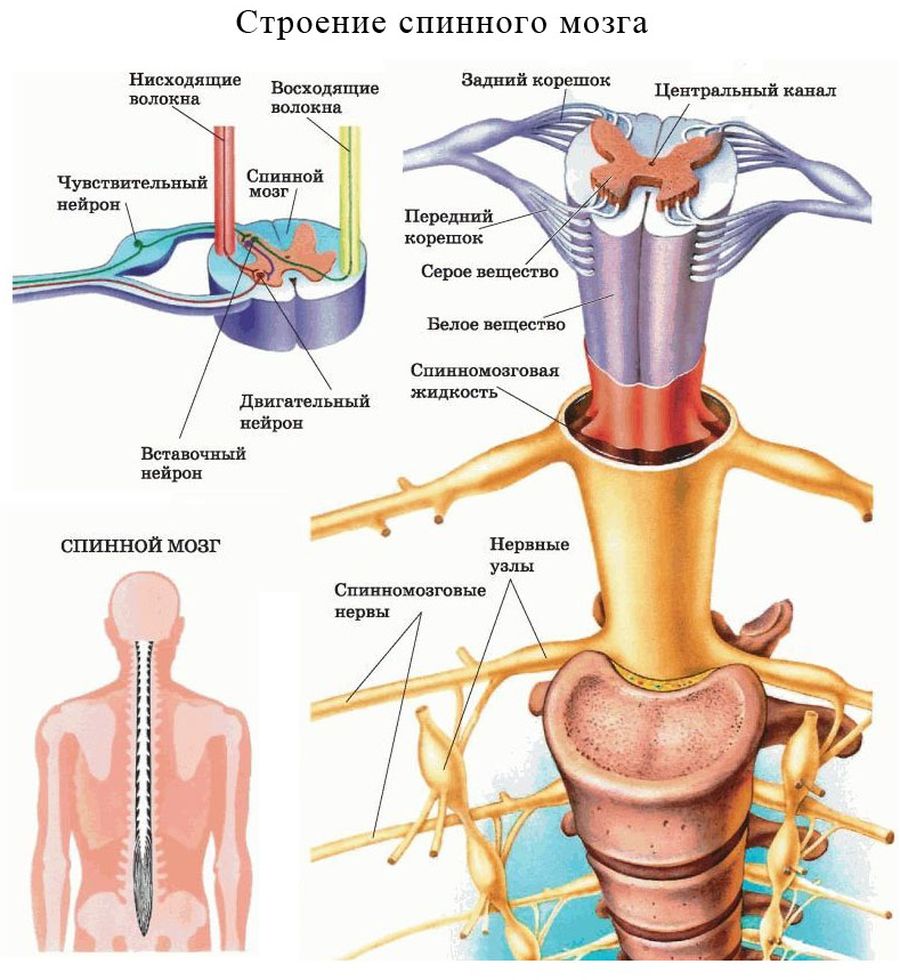

Спинной мозг и двигательная активность: Важные аспекты